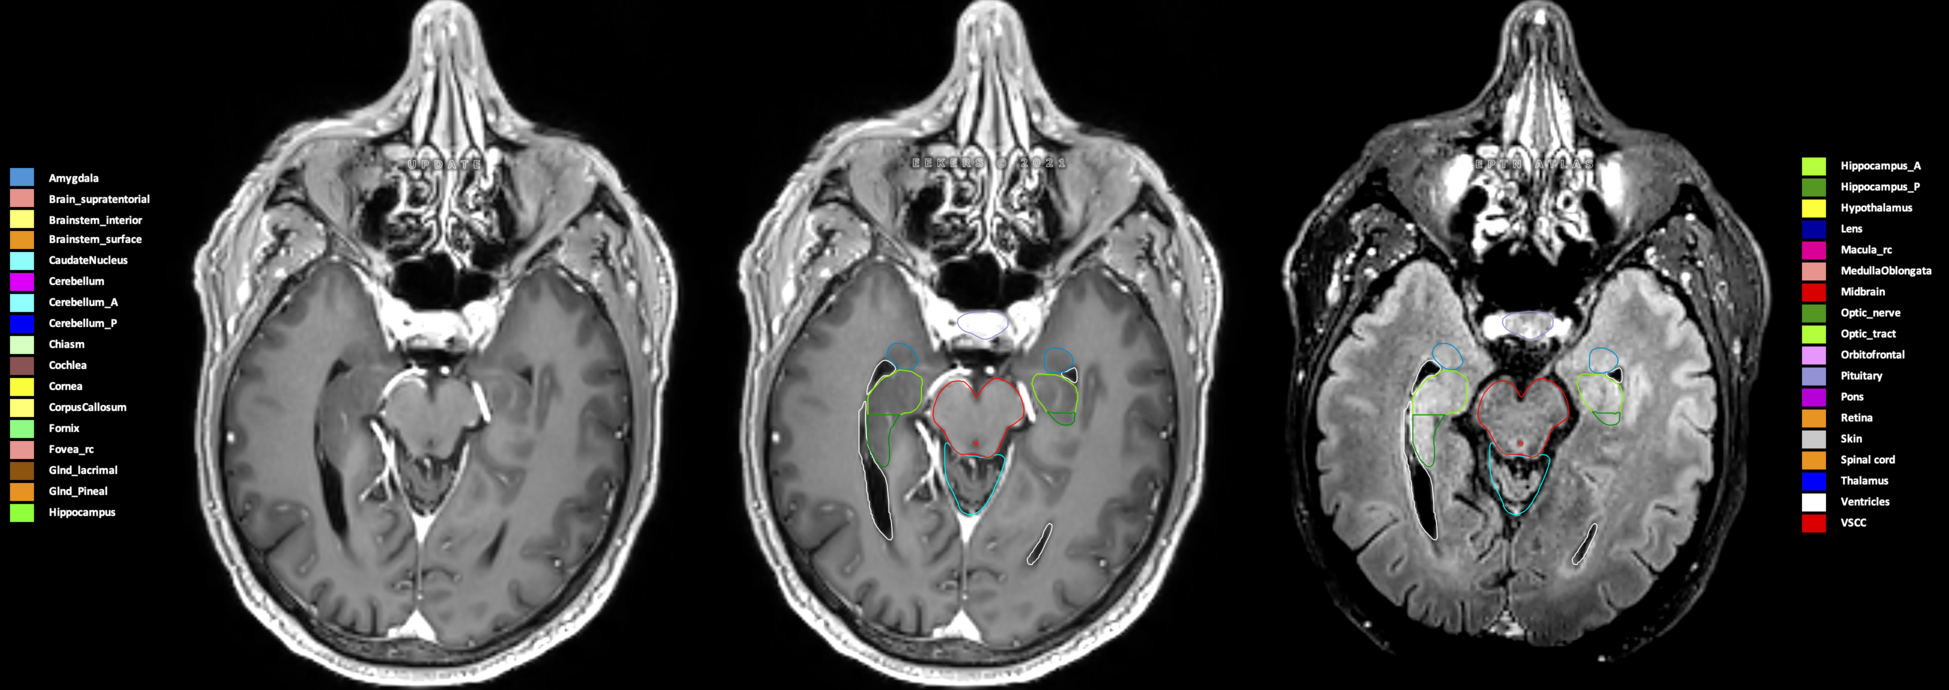

Eekers et al. have published an international neurological atlas for contouring of organs at risk in consensus with the European Particle Therapy Network (EPTN) in 2018 and an update in 2021. The purpose of this consensus atlas is to decrease inter- and intra-observer variability in delineating OARs relevant for neuro-oncology.

Included are all OARs known to be relevant for radiation-induced toxicity in neuro-oncology: brain, brainstem (midbrain, pons, medulla oblongata), chiasm, cerebellum (anterior & posterior), cochlea, cornea, hippocampus (anterior & posterior), hypothalamus, lens, lacrimal gland, optic nerve, pituitary, skin, and vestibular & semicircular canals. To further facilitate research on cognition, vision and radiological changes after irradiation of the brain, potential clinically-relevant OARs are included: amygdala, caudate nucleus, cerebellum (anterior & posterior), corpus callosum, fornix, macula, optic tract, orbitofrontal cortex, periventricular space (PVS), pineal gland, and thalamus.

Three-dimensional delineation of the 25 consensus OARs for neuro-oncology are shown on CT (WW/WL 120/40, 3000/600), 3T MR images, (T1Gd, T2FLAIR 1mm) and 7T MR (MP2RAGE 0.7 mm). All are presented in transversal, sagittal and coronal view.